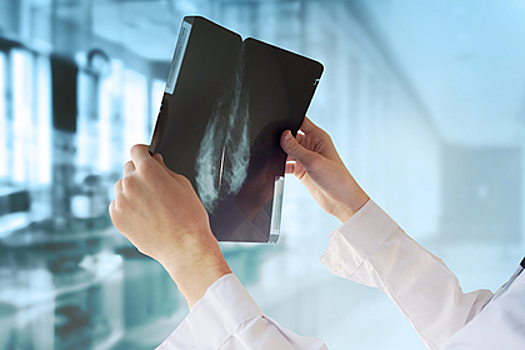

Эксперт утверждает, что рак молочной железы — один из наиболее распространенных видов злокачественных опухолей у женщин. Однако из-за недостаточной осведомленности девушки не знают истинных причин, по которым может возникнуть это заболевание, отметил врач.

По словам маммолога, его пациентки часто ошибочно считают, что рак могут спровоцировать травмы груди. Он объяснил, что из-за повреждения желез может возникнуть некроз жировой ткани, который при маммографии может напоминать злокачественную опухоль. Однако, заверил Колосовский, с помощью пункционной биопсии можно уточнить диагноз.